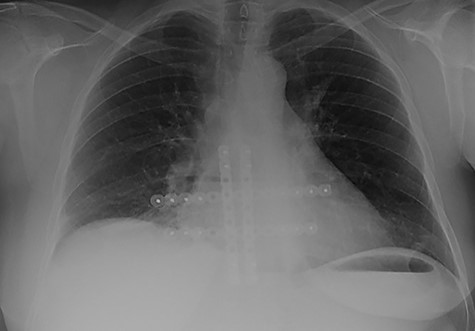

The second case at our institution was a 52-year-old woman with a history of left breast carcinoma treated for which she had undergone left wide local excision and sentinel node biopsy. Due to uncertainty regarding margins, she required a re-resection of her left breast tissue. She completed adjuvant radiotherapy and received maintenance hormonal therapy. She presented 8 months following her radiotherapy with sternal pain and positron emission tomography–computed tomography (PET–CT) imaging demonstrated localized uptake within the sternum (Fig. 3). Biopsy demonstrated proven recurrence of metastatic breast cancer. She was seen in clinic and counselled for partial sternectomy and reconstruction. She underwent partial sternectomy and underwent reconstruction with Synthes® plates. Her post-operative recovery was unremarkable. Post-operative histology was consistent with metastatic breast carcinoma, which was completely excised. The patient made an uncomplicated recovery and was seen in the outpatient clinic with a satisfactory post-operative chest radiograph (Fig. 4).